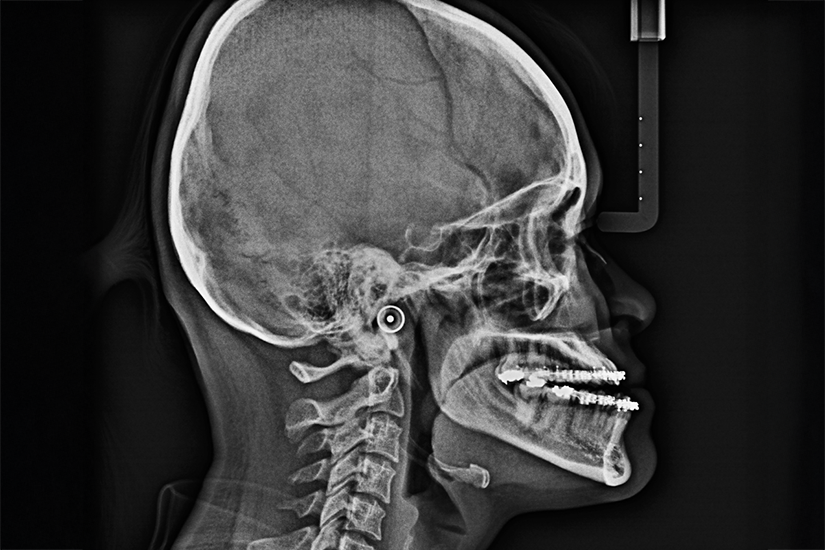

- Imagistică: radiografiile, mai ales cele cefalometrice, sunt esențiale pentru a evalua structura osoasă și relațiile dintre maxilare. Tomografia computerizată poate oferi imagini 3D detaliate ale structurilor cranio-faciale.

- Măsurători cefalometrice: acestea permit cuantificarea exactă a diferențelor dintre maxilare și evaluarea severității prognatismului mandibular sau maxilar.